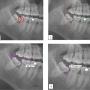

Caries and impacted MTM impaction: (1) Distal caries on MSM; (2) The depth and space of MTM was determined by the Pell & Gregory classification method; (3) The Shiller classification applied in determining the angulation of impacted third molar; (4) The distance between the distal CEJ of the MSM and mesial CEJ of the MTM was calculated as described in Leone classification

Original Article Page 776 - 787

The Incidence of Mandibular Second Molar Distal Caries Associated with Impacted Mandibular Third Molar: A Retrospective Study and Management Guidelines